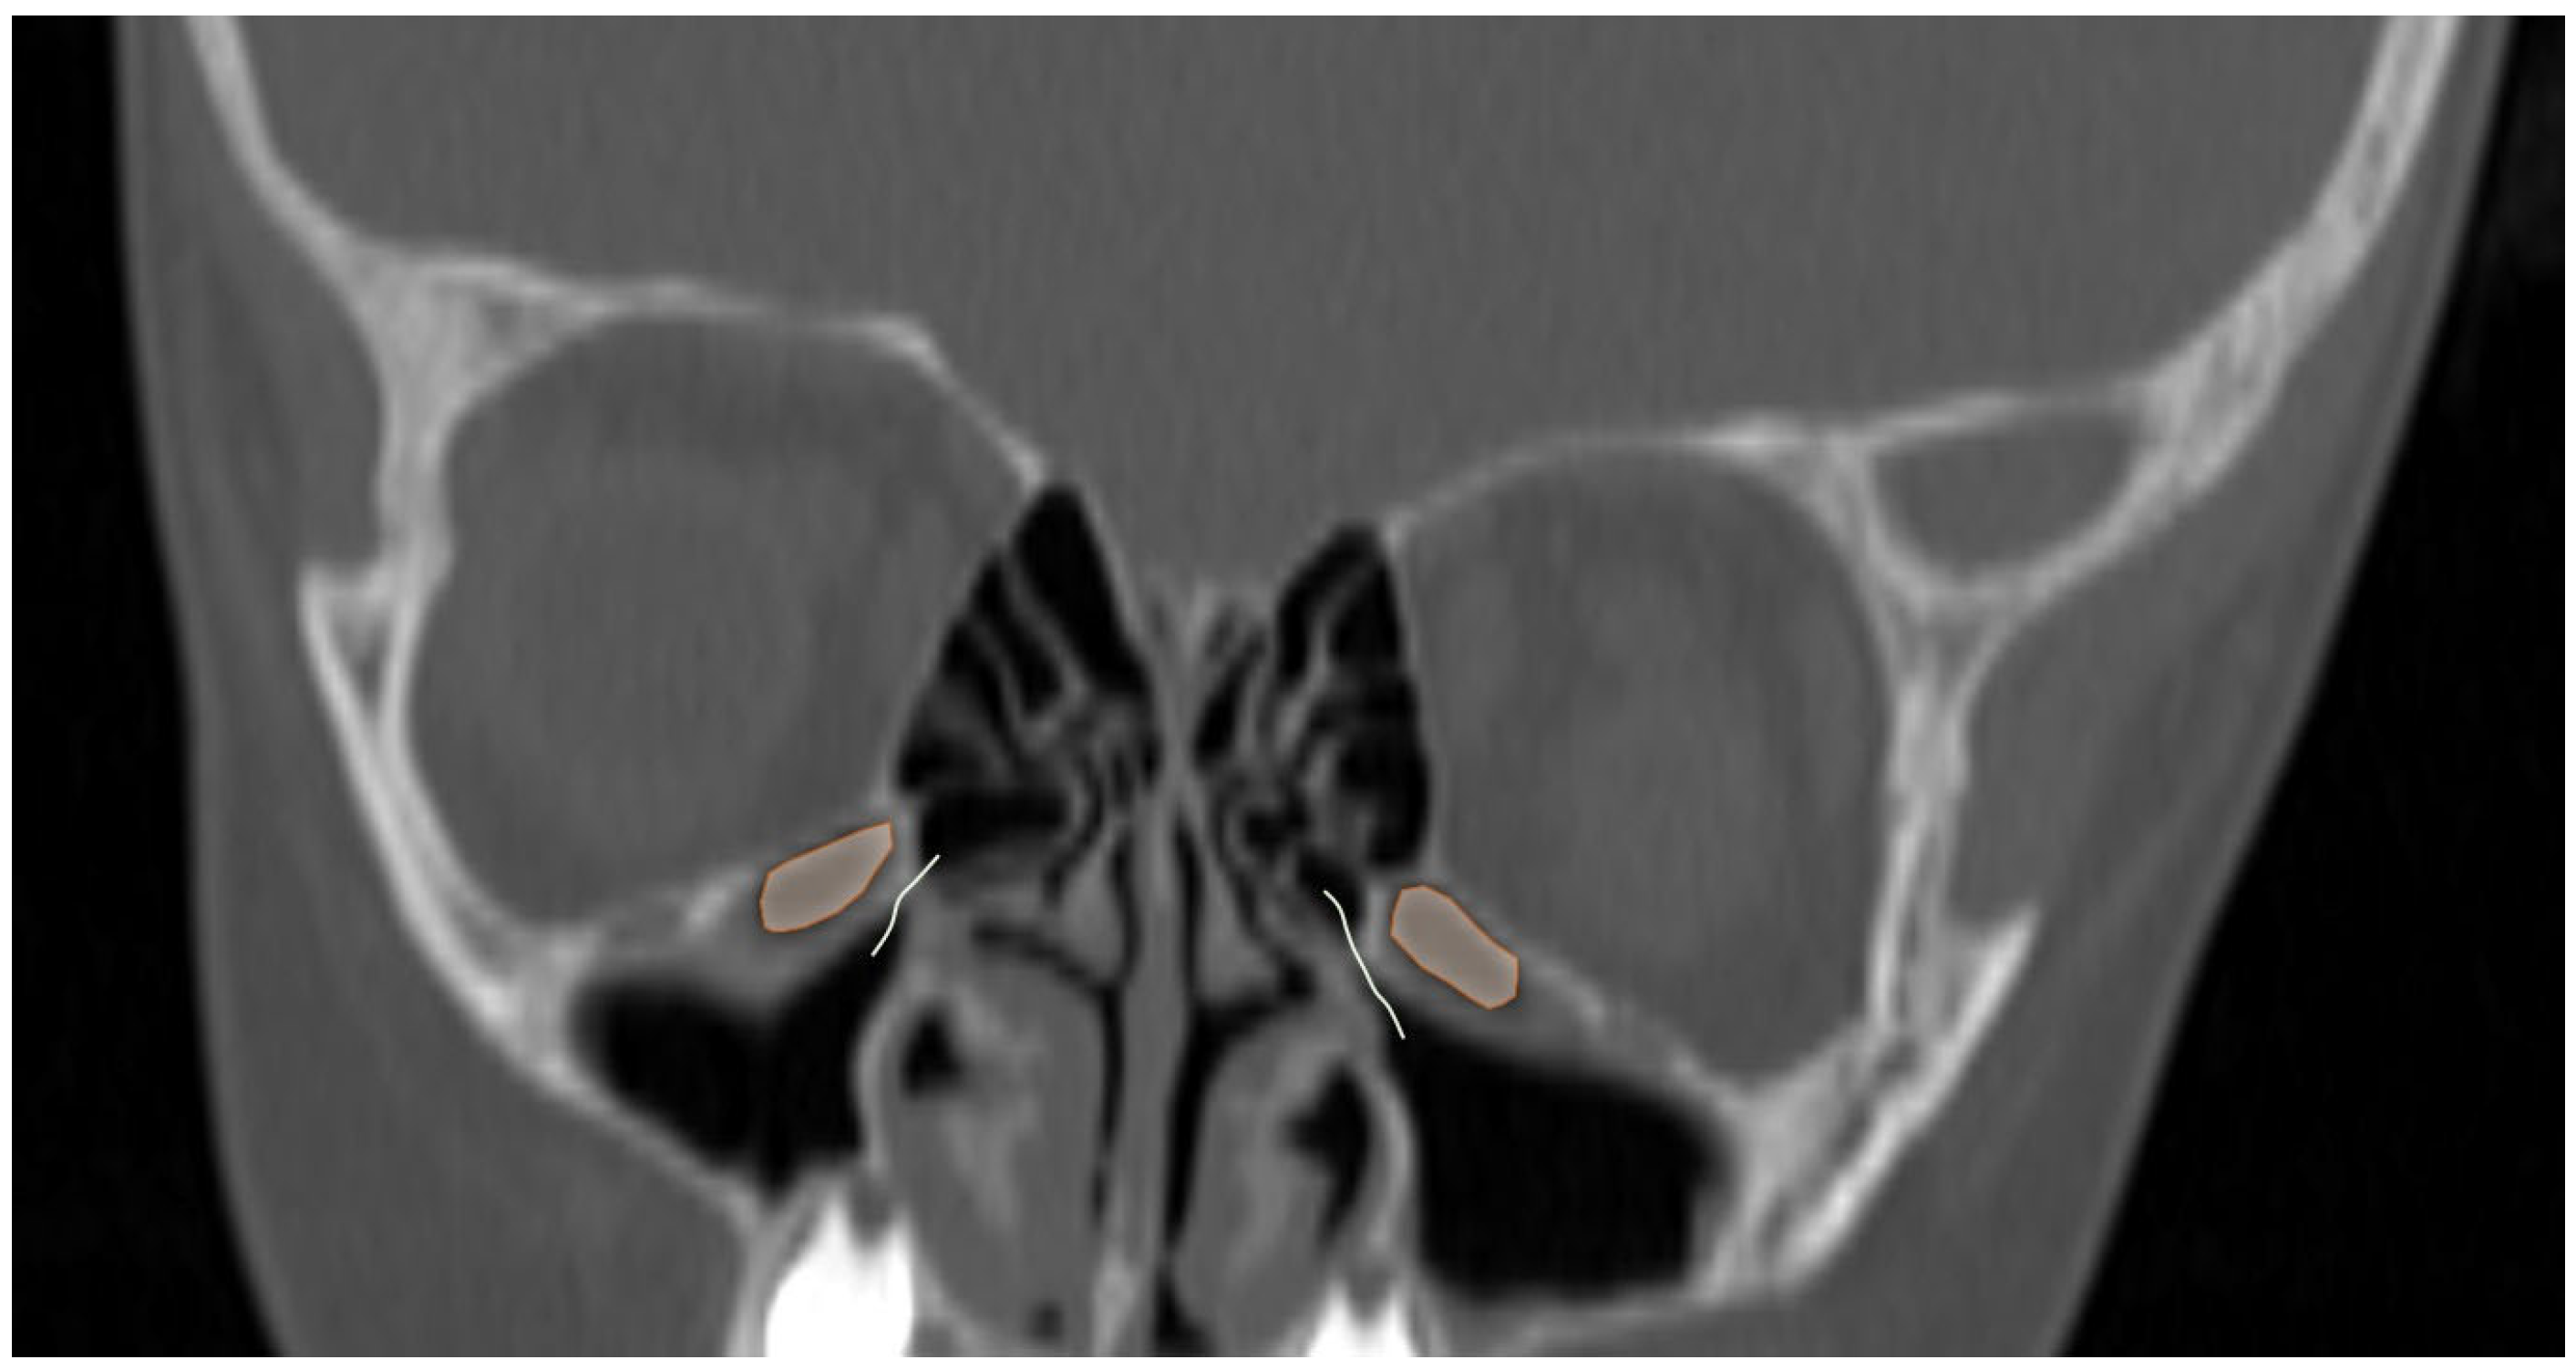

Additionally, the images were assessed for the presence of anatomic variants of the nasal cavity and PNS. Sinonasal variations were defined based on the European Position Paper on the Anatomical Terminology of the Internal Nose and Paranasal Sinuses [19]. According to this paper, the maxillary sinus is located between the orbital floor and alveolar process of the maxilla; the sphenoid sinus is the pneumatization of the sphenoid bone posterior to the rostrum; and the frontal sinus is defined as the pneumatization superior to a noticeable frontal beak [11,19]. The ANs are defined as the aeration of the protuberance on the lateral nasal wall, slightly anterior to the middle turbinate attachment (Figure 4). The Haller cell is an ethmoidal air cell, located below the orbital floor and lateral to a line parallel with the lamina papyracea (Figure 5). Onodi cell is the posteriorly located ethmoidal cell which develops just above and lateral to the sphenoid sinus (Figure 6). Concha bullosa is the pneumatization of the vertical segment of the middle turbinate (Figure 7) [19]. All anatomical variants were initially assessed by a single radiologist with four years of experience in maxillofacial CT imaging, who was blinded to patients’ demographic data, including age and sex. All assessments were done on a DICOM viewer (Medixant. RadiAnt DICOM Viewer [Software]. Version 2024.1. URL: https://www.radiantviewer.com (accessed on 1 November 2024)), after retrieval from the hospital PACS system to provide anonymized evaluation. The prevalence of each variant and the frequency of its bilaterality in each group were recorded. The evaluations were subsequently reviewed by a second radiologist with 11 years of experience. In cases of uncertainty regarding the presence of anatomical variations, a consensus decision was reached in consultation with a third radiologist with 13 years of experience.

Figure 5.

Coronal reformatted CT image of a 6-year-old girl with bilateral Haller cells (orange areas) narrowing the osteomeatal complex (curved lines).